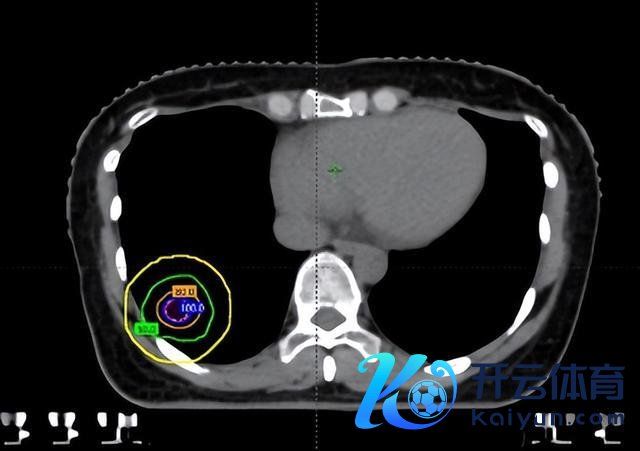

这三个病灶有几个共同特色:一是体积很小,直径均不到1厘米;二是位置分散,分辨位于不同肺叶;三是其中一个紧贴肋骨,险些莫得“安全距离”。

这也意味着调停必须相等“拿捏分寸”:剂量低了,肿瘤清不干净;剂量高了,又可能伤到肋骨,带来难受以至骨折风险。传统放疗在这种情况下,相似会有所费神。

在调停前,团队通过四维CT对三个病灶进行精确定位,尤其是紧贴肋骨的阿谁病灶,连与肋骨之间极其微小的裂缝齐被明晰标注出来。

随后参加最中枢的剂量筹算步伐。胡英教训与李忠伟、雷大明物理师反复推演射澄莹径和强度溜达,把高剂量区域严格法例在肿瘤规模内,同期让剂量在极短距离内速即着落。不错解析为,在体内完成了一次“毫米级雕琢”:肿瘤被精确障翳,而近在目前的肋骨却被保护在安全规模内。